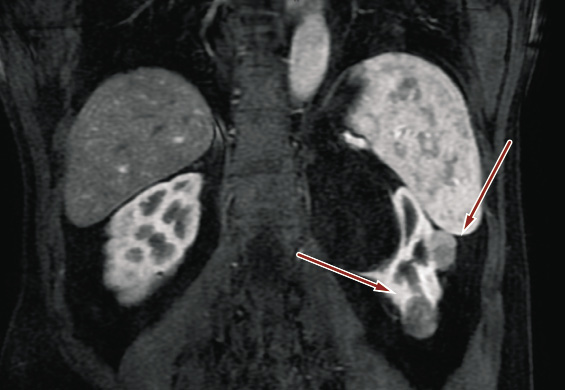

A 54-year-old Caucasian man was admitted to our Urology Clinic due to incidentally detected renal masses on the left side. His past medical history showed hypertension and hypercholesterolemia. He had no past surgical history. His renal functions and glomerular filtration rate were normal. Contrast-Enhanced Computed Tomography (CECT) revealed multi-focal hypodense renal masses and contrast enhancement. The features of the masses were suggestive of multiple renal cell carcinoma without dissemination (Figures 1 and 2).

Figure 2. Intravenous contrast abdominal computed tomography showing two contrast-enhancing solid lesions 20 mm in diameter (red arrow – the upper one) and 25 mm in diameter (red arrow – the lower) in the left kidney.

Tumor masses were located in the upper pole, middle renal, and in the lower pole of the kidney. Pre-operative risk in our institution was defined using PADUA and RENAL score. The lesion in the upper pole had a maximum diameter of 20 mm and had no communication with the urinary tract. PADUA score was 7p and RENAL score was 5a. The lesion located on the middle line had maximum diameter of 25 mm and was closed with the urinary tract, in fact PADUA score was 9a and RENAL score was 7a. The lower one had maximum diameter of 45 mm and reached urinary tract as well. Because of the size, it had PADUA score = 9a and RENAL score = 10a. According to TMN classification, the patient was classified as T2bN0M0 clinical stage. The Charlson comorbidity score was 0.